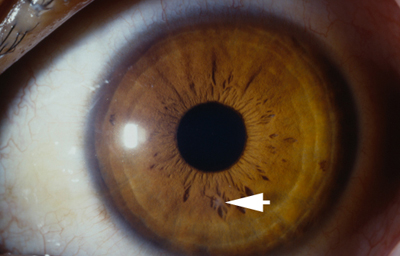

Al examen: Nubécula adelgazada “con aguijón desnaturalizado en córnea”; córnea sin edema con buena trasparencia y cámara anterior media. Iris con pupila negra, central y redonda con sinequia anterior de hoja anterior del Iris de 5 a 8 en periferia e Iridoschisis, sin pérdida de pigmento en el Iris . Cristalino trasparente, polo posterior bien. TO: 17 en ambos ojos aplanático de Goldman. (Fotos 26 y 27)

Foto 26 - Leucoma a las 2 con agujón “in situ

Foto 27 - Aguijón desnaturalizado